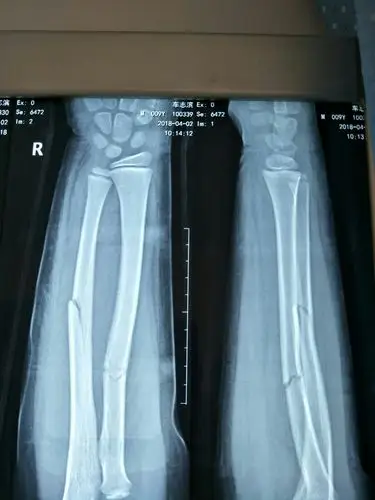

55岁胸12椎体压缩性骨折合并左尺桡骨粉碎性骨折手术一例

桡骨尺骨骨折,x线片

人类x光片显示桡骨骨折

一例桡骨远端粉碎性骨折